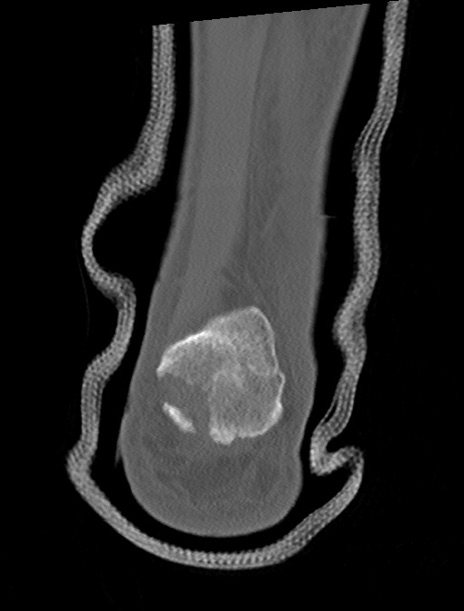

症例37 左足関節CT(冠状断像)

左足関節CT